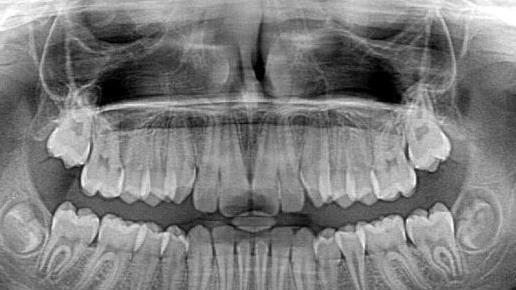

Vor 125 Jahren wurde die Röntgenstrahlung in Würzburg entdeckt. Sie gilt als großer und wichtiger Fortschritt in der Wissenschaft. Symbolfoto: jarmoluk/pixabay

Röntgenstrahlen sind extrem kurzwellige, energiereiche elektromagnetische Strahlen, die viele Materialien durchleuchten können. Sie sind für das Auge nicht sichtbar. Auf einem Röntgenbild sind Knochen gut zu erkennen, Weichteile nicht. In der Technik lassen sich mit ihnen Werkstoffe prüfen, im Labor die Struktur von Kristallen analysieren. Röntgenteleskope im Weltraum enthüllen energiereiche, kosmische Prozesse etwa bei Schwarzen Löchern.

Vor 125 Jahren gab es verwaschen aussehende schwarzweiß-Bilder, die von einem oder wenigen Ärzten betrachtet wurden. Heutige Computertomographen nehmen zahlreiche hochaufgelöste 3D-Bilder des Patienten auf. Medizintechnik-Unternehmen setzen bei der Analyse solcher Bilder zunehmend auf digitale Assistenten: Eine Software auf Basis künstlicher Intelligenz erkennt in den Bildern kleine Störungen oder Tumore und weist die Radiologen darauf hin.